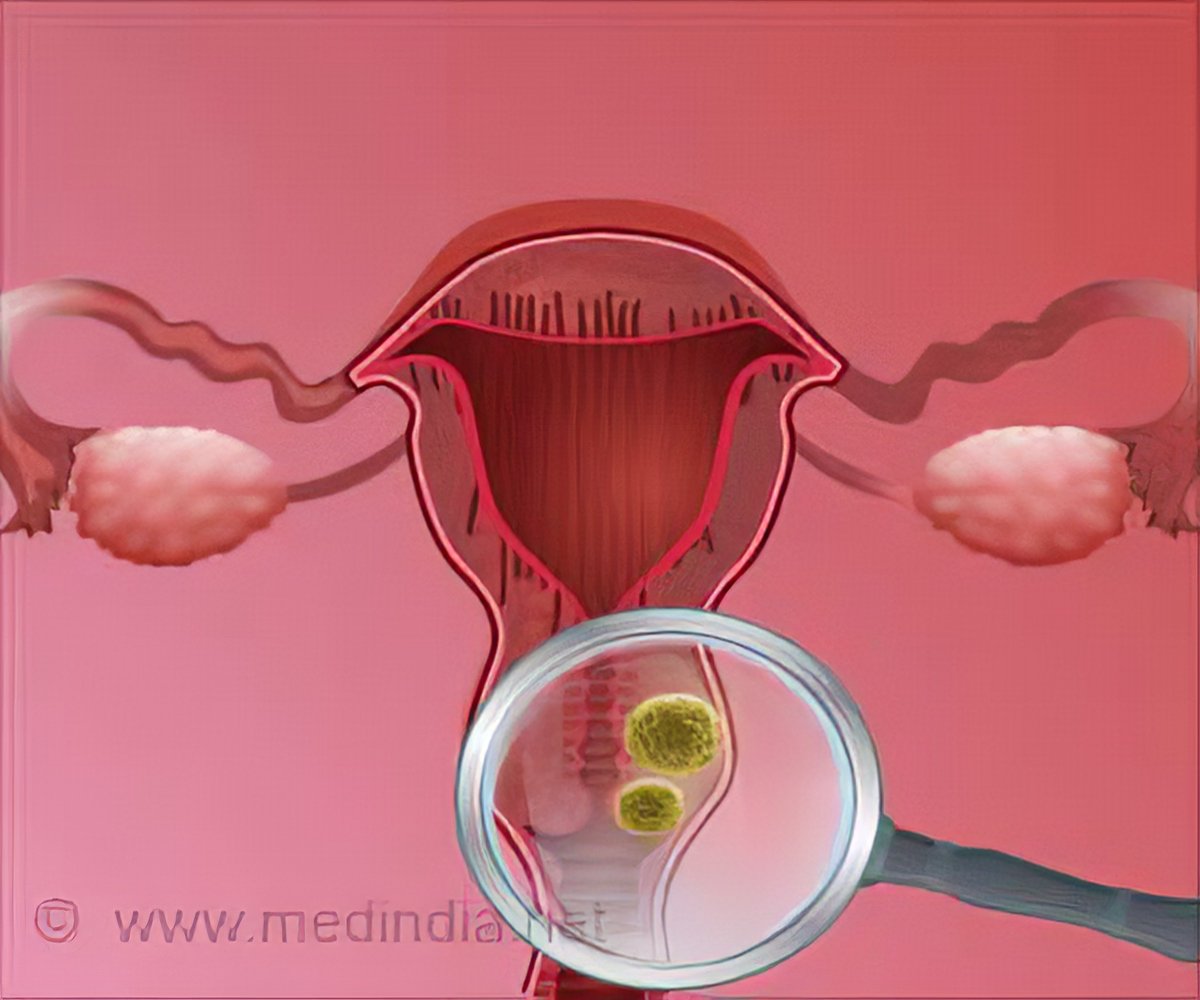

Факторы Риска ВПЧ: Визуальный Обзор и Информация